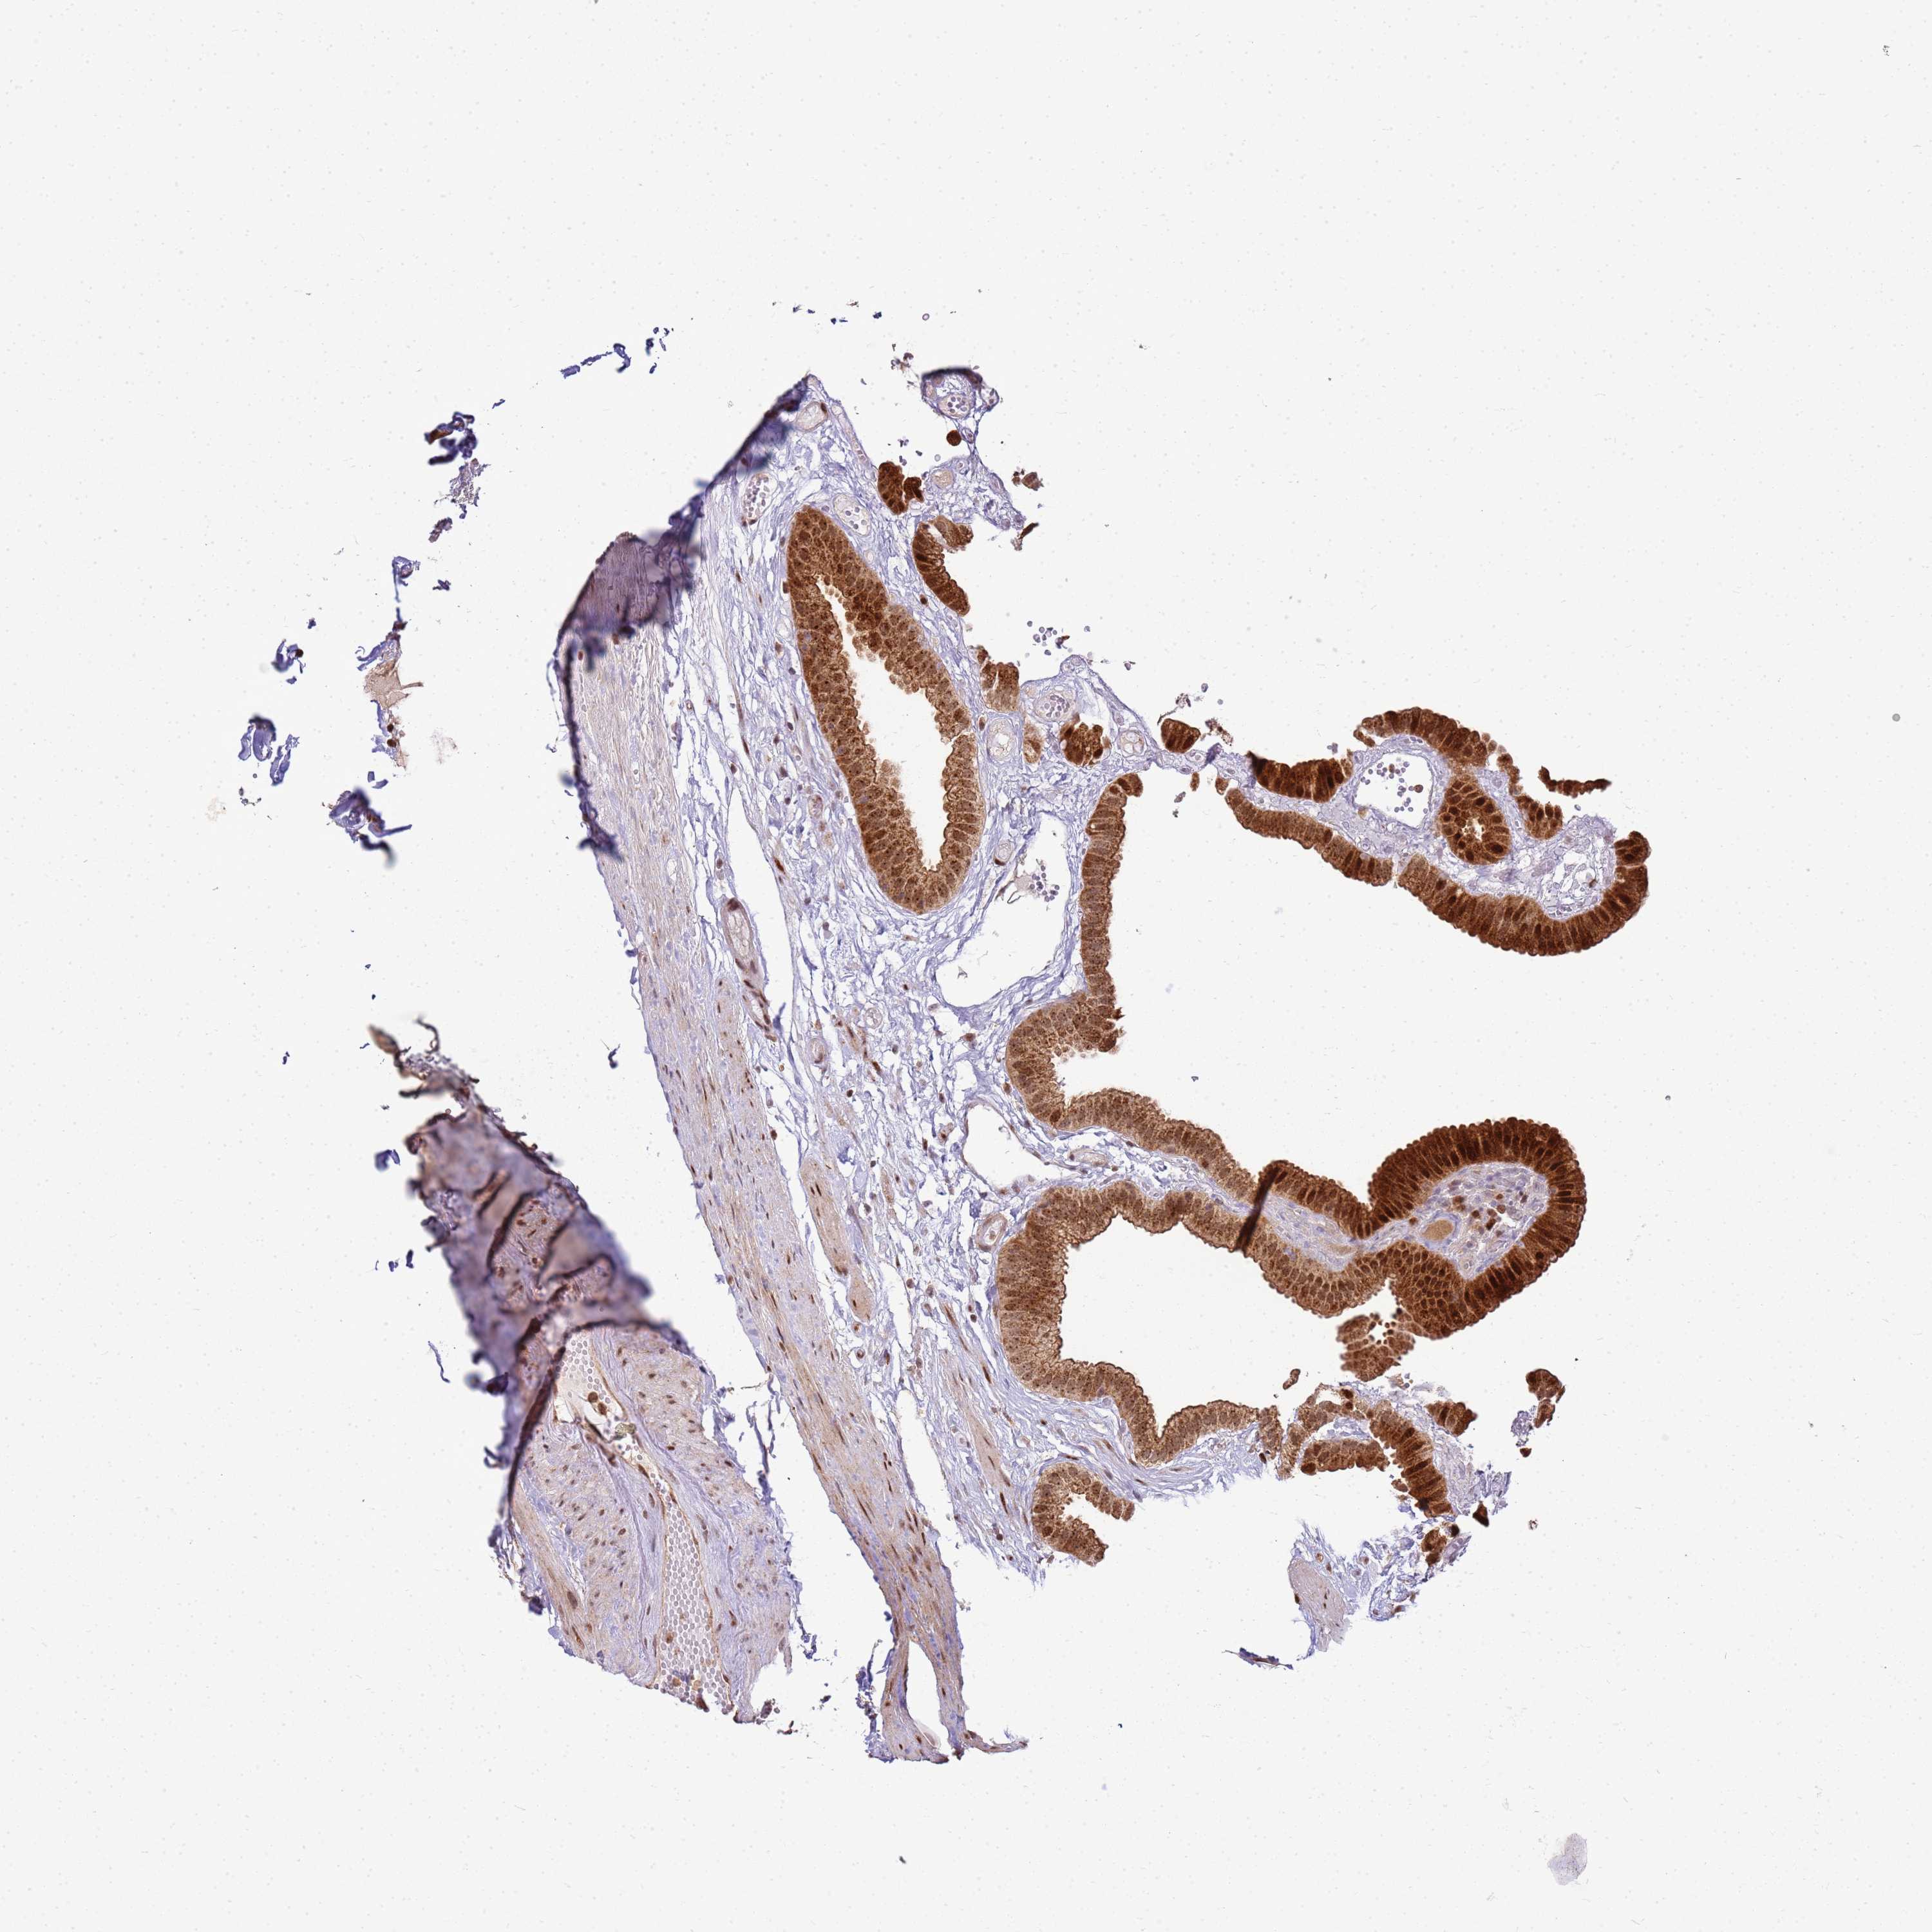

PEX14